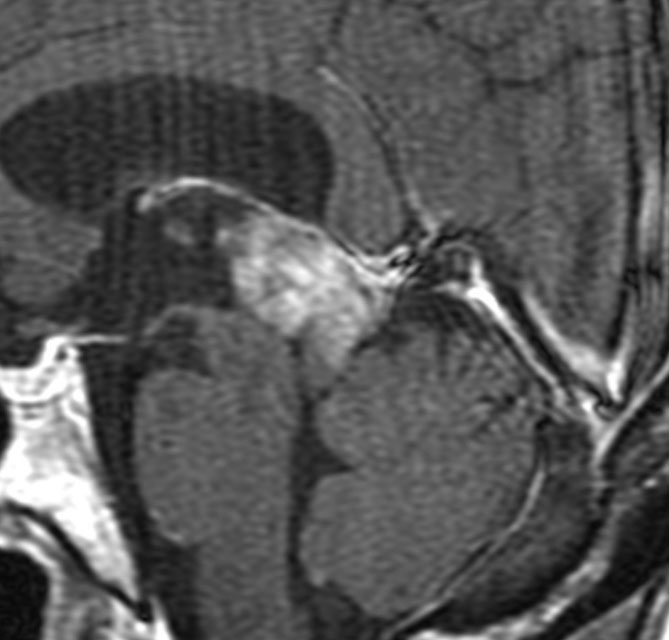

MRIガドリニウム増強像です。腫瘍境界がわりにはっきりしていて,中脳や視床に浸潤像がありませんから,松果体芽腫ではないことが解ります。でも,この画像だけからは,松果体細胞腫やジャーミノーマとの区別はつきません。